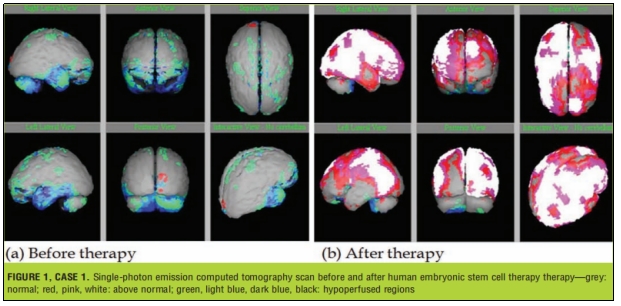

案例分享|3名自闭症患儿经干细胞治疗后、认知、言语和书写等能力得到明显改善

近期,Geeta Shroff等人进行了一项关于ASD的临床试验,该团队采用人胚胎干细胞 (hESC)治疗了3名ASD患者,随访显示,该疗法能有效提高ASD患者的运动技能、社交技能和认知等能力。